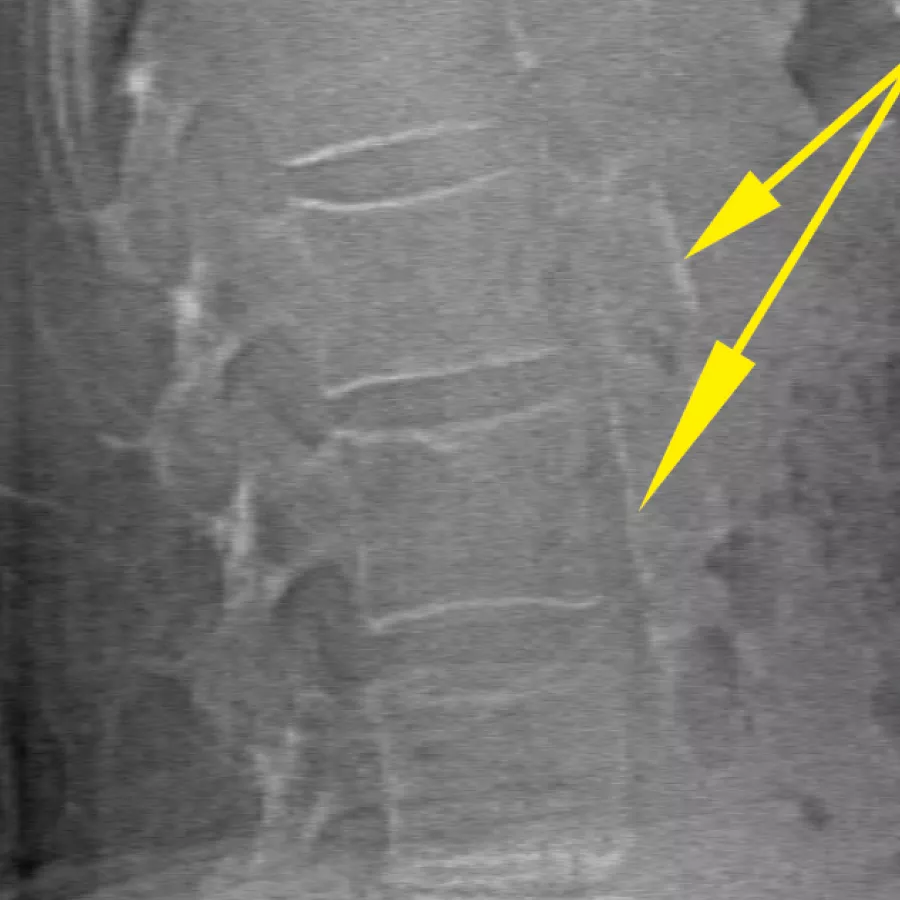

Improve accuracy and reduce post-exam analysis errors with precise, software-assisted placement of inter-vertebral disc spaces for graphic analysis.